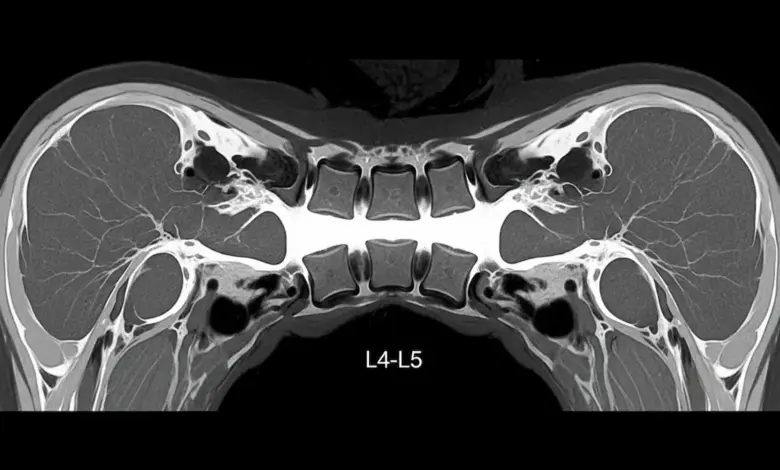

- A ressonância magnética costuma ser o exame mais útil para ver compressão neural, discos, ligamentos e inflamação associada.

- Tomografia pode detalhar estruturas ósseas, útil quando há dúvida anatômica ou planejamento cirúrgico.